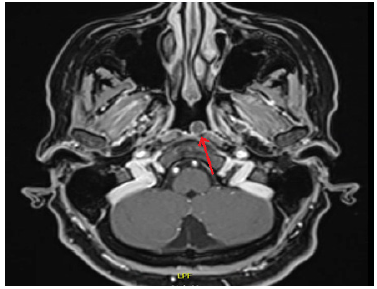

Mujer de 48 años de edad, con historia de tres meses de inestabilidad, en especial al realizar movimientos, y concomitantemente dolor y rigidez cervical. El examen clínico otorrinolaringológico fue normal, la audiometría mostró normoacusia y los exámenes vestibulares normales. Se solicitó resonancia magnética de fosa posterior con contraste encontrándose una lesión nodular en la nasofaringe de 0,7 cm de diámetro en T1 y T2, (figura 1A y B) que no varió con el contraste no afectando a estructuras óseas, sugerente de quiste de Thornwaldt (figura 2). Se realizó endoscopia nasal observándose una lesión regular lisa, de aspecto quístico en la nasofaringe (figura 3). Se decidió realizar marsupialización del quiste bajo abordaje endoscópico transnasal, se retiró los bordes y se cauterizó con electrocauterio, sin mayor complicación; el informe anatomopatológico descartó lesiones malignas informando solo tejido inflamatorio. El caso fue catalogado como quiste de Thornwaldt. La paciente presentó mejoría de dolor y rigidez cervical, aunque la inestabilidad se mantiene.

El diagnostico está basado en la endoscopia nasal y en imágenes, en muchos casos se encuentra de forma casual. En la endoscopia nasal, se observa una lesión redonda, de superficie lisa, de aspecto quístico (5,7). La tomografía, así como la resonancia son de gran utilidad, pero para algunos autores la resonancia se considera como el gold estándar para el diagnóstico, ya que se puede apreciar la lesión, la misma que resalta con gran intensidad tanto en T1 y T2, por el contenido proteico y hemorragias que presenta el quiste aun sin contraste con gadolinio (4,6,9,10).